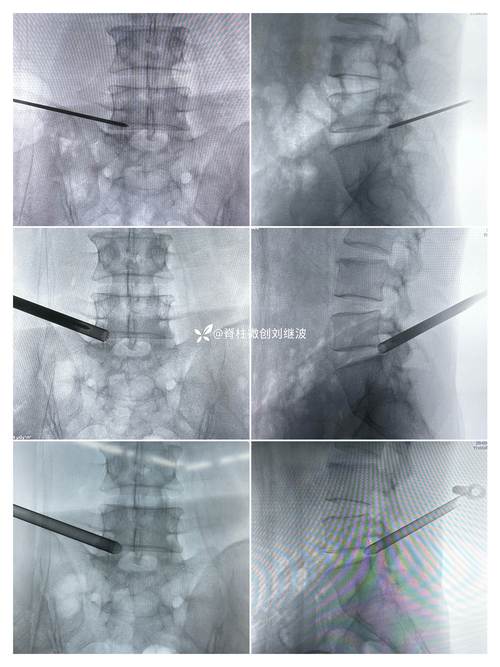

临床优势方面,德国思科椎间孔镜系统以“精准、安全、高效”为核心特点,数据显示,其手术时间平均为60-90分钟,较传统开放手术缩短50%以上;术中出血量控制在5-10ml,无需输血;术后患者下床时间提前至6-12小时,住院时间缩短至3-5天,长期随访显示,术后优良率(MacNab标准)达85%-92%,复发率低于3%,系统兼容性强,可与C臂机、O臂等影像设备联动,支持个性化手术规划。

市场应用中,德国思科椎间孔镜系统在全球三甲医院及脊柱专科中心广泛使用,其设备已进入北京积水潭医院、上海长征医院等顶尖医疗机构,并被纳入多地医保报销目录,近年来,公司结合中国医生操作习惯,开发了“亚洲版”套管系统,调整了手柄角度与器械长度,进一步提升了本土化适配性。